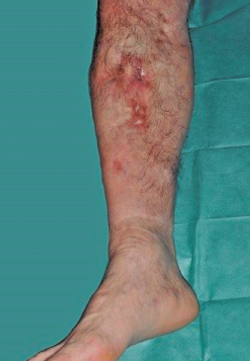

Se trata de un paciente varón de 57 años con antecedente de fractura abierta de tibia-peroné que evolucionó hacia la infección, requiriendo múltiples intervenciones hasta la consolidación de la fractura. Al cabo de 20 años se produce recidiva de la infección presentando fístula productiva al nivel de la cara medial del tercio proximal de la pierna (Figura 1).

Figura 1. Fístula productiva en la cara medial del extremo proximal de la pierna.